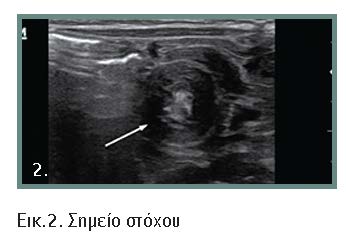

Η διάγνωση τις περισσότερες φορές είναι προφανής, όμως υπάρχουν άτυπες μορφές που μπορεί να προβληματίσουν τον κλινικό ιατρό (εικόνες 1, 2, 3, 4). Αλυσιδωτές επιπτώσεις στον οργανισμό συνθέτουν την κλινική εικόνα και τις επιπλοκές της νόσου. Με την εξέλιξη της κλινικής εικόνας και όσο δεν αντιμετωπίζεται η απόφραξη, μπορεί να εμφανιστούν βαρύτατες οξεοβασικές και ηλεκτρολυτικές διαταραχές. Οι διεγχειρητικές επιπλοκές πρέπει να αναγνωρίζονται και να αντιμετωπίζονται αμέσως γιατί οι επιπτώσεις είναι μοιραίες.